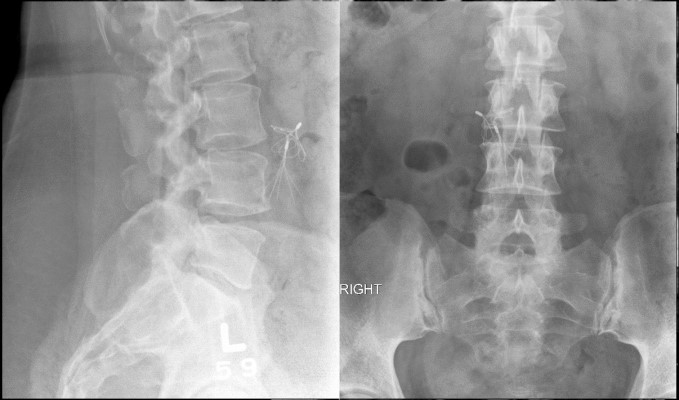

Preliminary lumbar spine x-ray showing mold degeneration at L5/S1